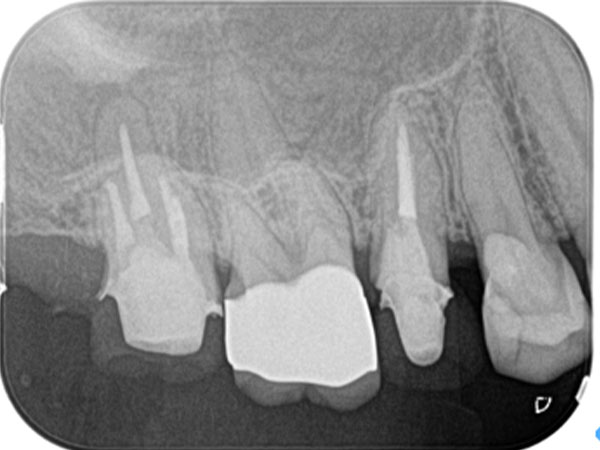

下の写真をご覧ください。歯の中に見える黒い部分が「根管」です。根管の形は複雑で、患者さんひとりひとりによって異なります。しかも細いところは直径1mmもありません。こんなに狭くて複雑な根管から、感染部位を正確に取り除くというのは困難を極めます。

複雑な根管を治療するには、事前の画像診断で根管の形状を可視化することが重要です。多くの歯科医院では、画像診断に「2次元」のレントゲンが用いられますが、レントゲンでは初期の患部を見つけにくい上に、根管の複雑な形状をしっかり可視化するほどの力はありません。

そこで、当院では3次元で撮影ができる「CT」を利用します。CTはあごの骨の中を立体的に可視化するので、レントゲンには写らない患部の様子までがしっかりわかります。日本国内の歯科医院での、CTの普及率は5〜10%程度と言われています。